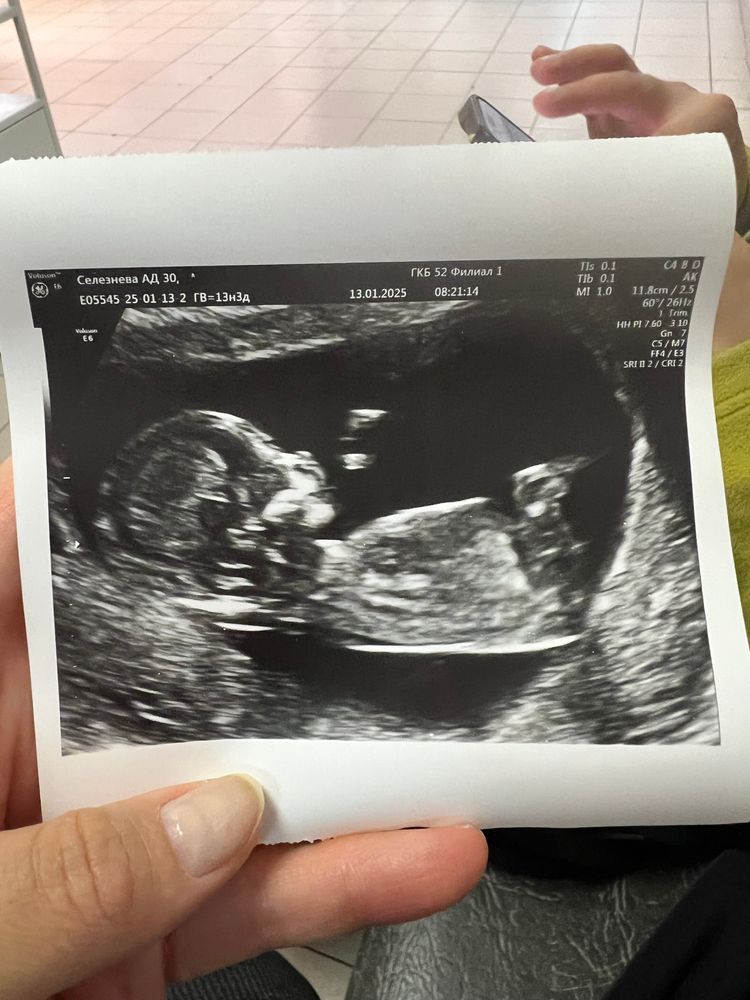

Девочки, всем привет! Знаю что еще рано, но очень любопытно. Сегодня были на первом скрининге на сроке 12.6

врач предположила пол только по поведению малыша (так как мешала пуповина и не показывался) - спокойная как девочка. Может кто то посмотреть и предположить кого видно 🙏🏻😀 понимаю что качество плохое 😅

у вас ракурс такой, что невозможно предположить))) нужен ракурс в профиль, где смотрят носик и воротниковую зону. Там видно половой бугорок.